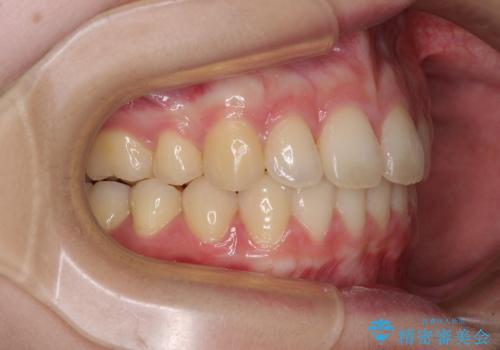

左側の咬み合わせと上下正中の位置をコントロールするために時間がかかりましたが、事前に思い描いた通りの歯列に整い、患者様には大変満足していただきました。

上下の咬み合わせは、下顎に対して上顎が相対的に前方にあったため、奥歯のシザーズバイト改善後に上顎左右第一小臼歯2本を抜歯し、上顎前突を改善していくこととしました。